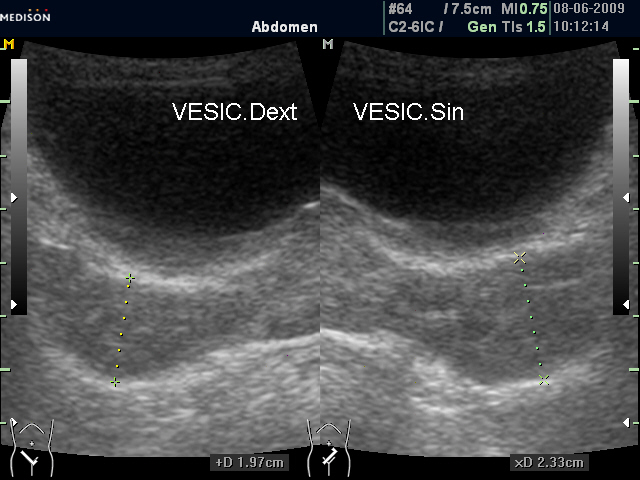

И еще "вдогонку", из вчерашнего. Правый СП 19,7 мм, левый - 23,3 мм.

Утолщенные "рыхловатые" немного асимметричные СП (ТА УЗИ)